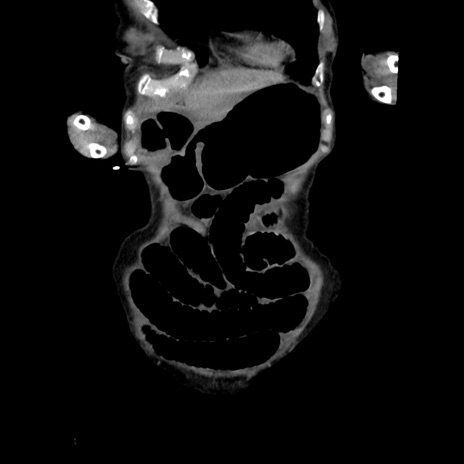

横断像

【症例】80歳代女性

【主訴】嘔吐、腹痛

【現病歴】数時間前より嘔吐あり。心窩部痛出現し、徐々に右下腹痛あり。その後も数回嘔吐あり救急搬送となる。

【既往歴】左大腿骨頚部骨折手術

【身体所見】腹部は膨隆しているが軟らかく圧痛なし。腸雑音はやや亢進。

【データ】WBC 12000、CRP 19.05